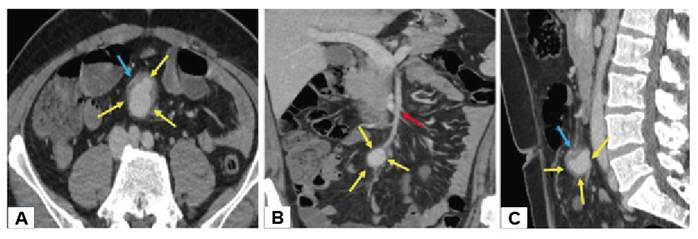

Mycotic Aneurysm of the Superior Mesenteric Artery due to Infective Endocarditis.

感染性心内膜炎引起的肠系膜上动脉真菌性动脉瘤。